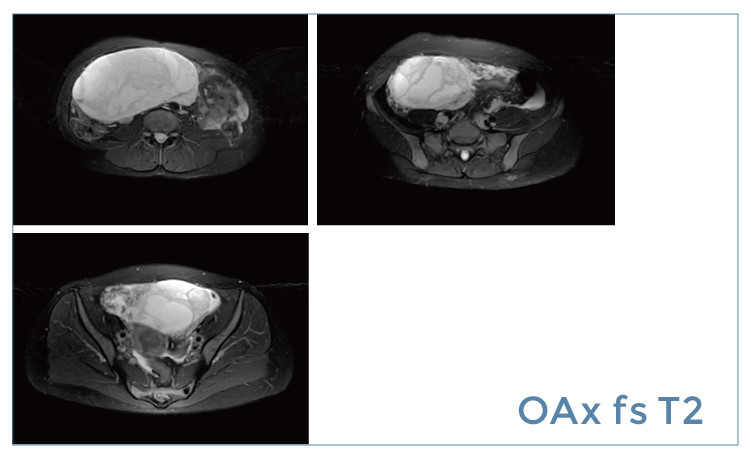

【朗润影像档案】20190419磁共振影像病例结果讨论